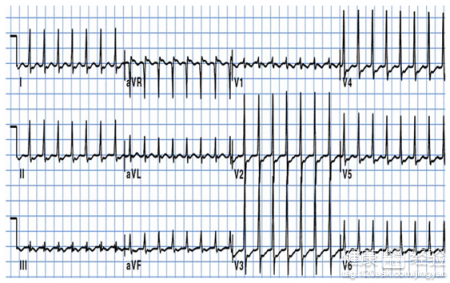

心動過速是現在很多人都會患上的疾病,現在社會中,由於空氣污染加大,人們生活壓力加大等等問題,多種因素如感染、物理和化學因素均可引起心動過速。若是我們患上了心動過速,就應該積極的配合治療,不能看症狀比較輕,就不重視,不然的話,可能會造成更加嚴重的後果,造成大麻煩的,只有我們積極的配合治療,才能讓身體恢復健康。心動過速的表現有哪些?

1心動過速的表現主要是心跳明顯的加快,人會感覺到精神高度的緊張,可能會出現渾身虛汗等問題,也有可能發生頭痛等問題,是很不好的,若是發現這種情況,我們應該盡早的檢查一下你的身體情況。

2心動過速的表現,還有就是胸痛,大多數病人疼痛劇烈甚至難以忍受,有瀕死感,持續時間有時不是很長但有的時候疼痛甚至好幾天。若是有這種感覺的患者,應該積極的配合治療,才能讓你的身體更加的健康。

3心動過速的表現,可能引起疲勞,很少有患病後更覺渾身是勁的情況,不同疾病引起不同程度的疲勞,若是感覺到自己的體力下降,明顯疲勞的感覺的話,就應該盡早的去醫院進行檢查了。